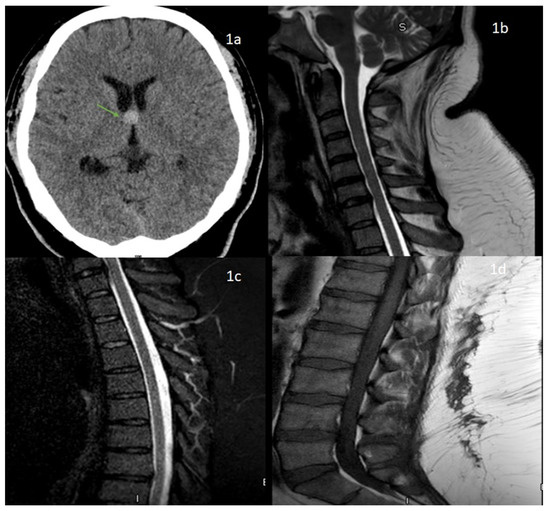

A 41-year-old morbidly obese gentleman with no significant medical history presented to the emergency department (ED) with acute onset of urinary retention twelve days after his COVID-19 vaccination (Janssen vaccine). The patient only reported arm soreness, mild fatigue, and chills three days after the vaccination which were self-resolving in a few days. He underwent evaluation in the ED followed by urinary catheterization and was followed up with urology as an outpatient. On day 15 following his COVID-19 vaccination, he returned to the ED with a new onset of left-sided facial droop. He was diagnosed with Bell’s palsy and was discharged with prednisone and valacyclovir. His CT brain showed a colloid cyst and, hence, he was referred to see neurosurgeons as an outpatient (Figure 1).

Figure 1.

(1a) CT head showing colloid cyst at the level of foramen of monroe (green arrow). (1b,1c) MRI cervical and thoracic spine sagittal images showing no abnormal intramedullary cord signal changes. MRI lumbar spine (1d), T1 weighted sagittal image showing no degenerative disc disease.

An MRI of the cervical and thoracic spine did not show any abnormal T2 signal changes and his lumbar spine showed no significant degenerative disc disease (Figure 1). He underwent lumbar puncture due to suspicion for Guillain-Barré syndrome (GBS) and showed albumino-cytological dissociation with a CSF cell count of 50/uL (lymphocytes 91%, monocyte 9%, red blood cell counts of 123) and CSF protein of 562 mg/dL. Further corrected cerebrospinal fluid (CSF) protein for the presence of RBC was significantly elevated to 562 mg/dL. Other CSF findings included glucose of 67 mg/dL (serum glucose 109 mg/dL) and negative CSF gram stain, CSF lyme polymerase chain reaction (PCR), and viral PCR testing on CSF, including herpes simplex virus, varicella zoster virus, Epstein-Barr virus, cytomegalovirus (CMV) and Borrelia burgdorferi IgM and IgG. Given the classic clinical picture of GBS in absence of other identifiable etiology for his neurologic disease, additional supportive testing with EMG showed a prolonged distal latency with conduction block and slow conduction velocity in bilateral tibial, peroneal nerve, and absent F waves were supportive for demyelinating GBS. He was started on intravenous immunoglobulin (IVIG) at 2 g/kg over 5 days. Other notable laboratory findings included a white cell count of 15.0 × 109/L, possibly due to recent steroid use and borderline elevated D-dimer. The erythrocyte sedimentation rate, creatine phosphokinase, blood glucose, hepatic and renal function, vitamin B12, folate levels, and thyroid-stimulating hormones were all within normal values, whereas the serum HIV test was negative. Chest X ray was unremarkable with no hilar or mediastinal lymphadenopathy.